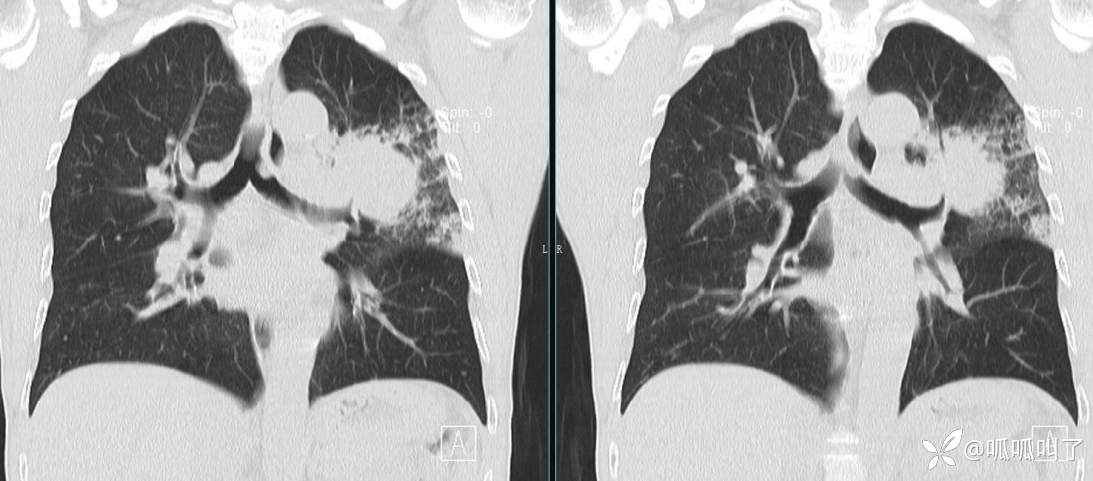

胸部CT平扫和增强: